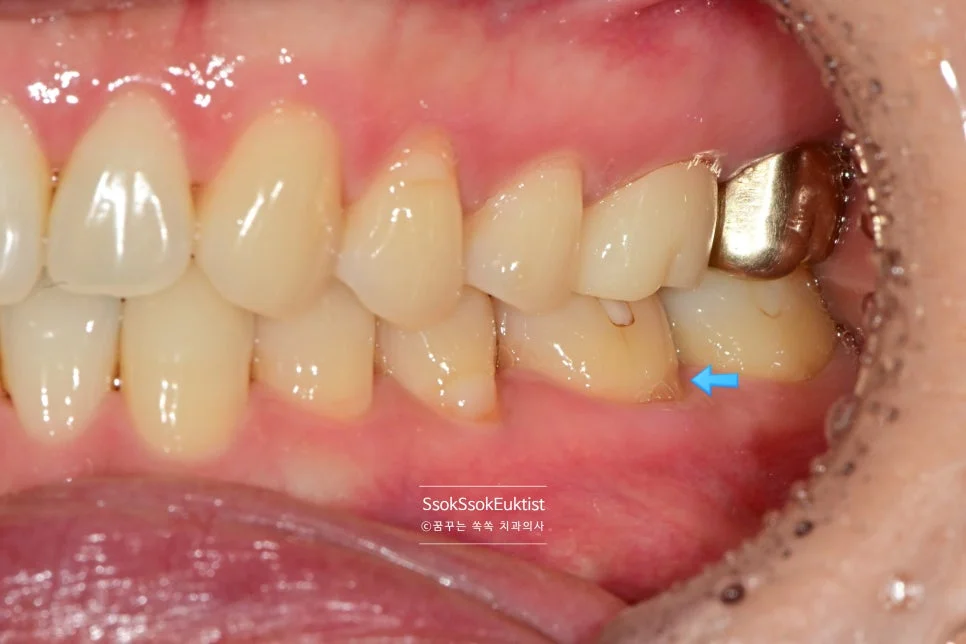

레진 치료 전 — V자 형태의 치경부 마모증

치아의 목 부분이 패여져 있는 모습입니다. 형태를 보면 U자라기보다는 V자에 가깝고, 즉 강한 교합력에 의해 치아 목 부분이 패였네요.

레진은 플라스틱 재료로 치아와 색상을 아주 잘 맞출 수 있습니다. (그렇다고 아무나 잘 맞추는 것은 아닙니다^^)